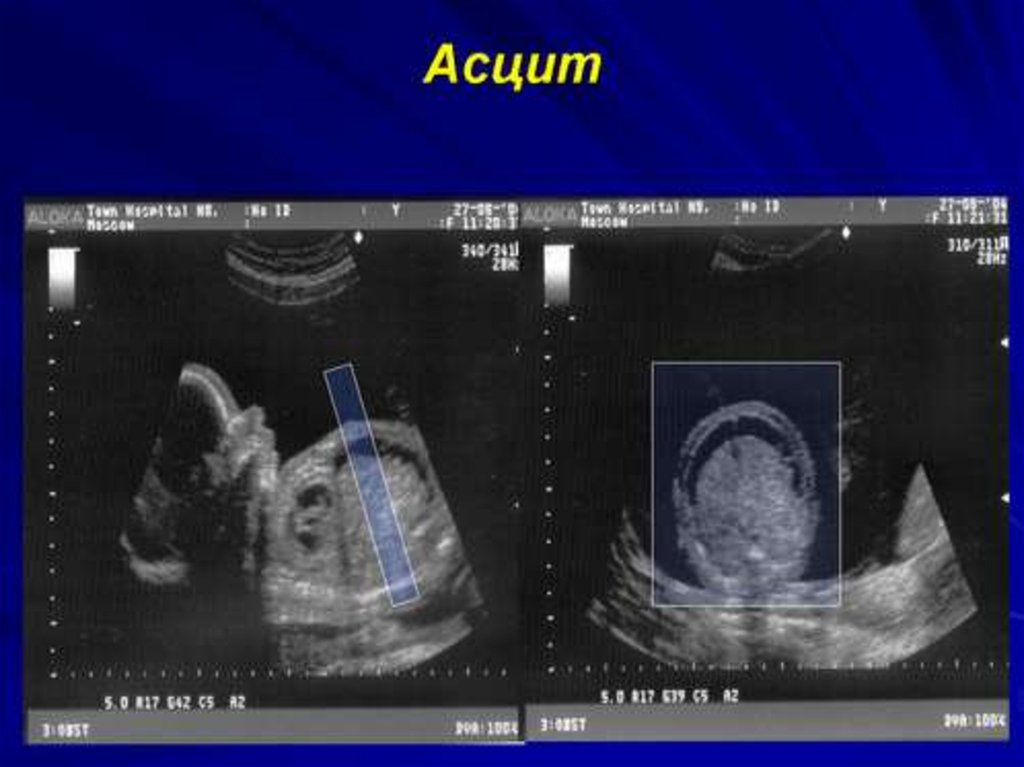

Пренатальная диагностика

1. ПРЕНАТАЛЬНАЯ ДИАГНОСТИКА